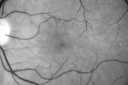

67-year-old woman has a macular pucker in the left eye. She had radiation for a melanoma in that eye in 2006. She had cataract surgery February of 2009 and a posterior sub-Tenon Kenalog injection in April. Her vision in the left eye is hazy and she has trouble seeing out of it. VISUAL ACUITY: OS 20/70. IOP: 11. The posterior chamber intraocular lens is in good position. EXTENDED OPHTHALMOSCOPY: OS: Vertical C/D ratio is 0.3. There are 2+ vitreous cells. There is a 3+ epiretinal membrane. There is radiation and retinopathy nasal to the optic nerve and there is a melanoma, which has regressed superonasally. OCT SCAN: The OCT scan shows an average central foveal thickness of 347 microns, which is stable. Photos confirm clinical findings. FLUORESCEIN ANGIOGRAPHY: Fluorescein angiography shows some irregularities where the macular pucker is and the radiation retinopathy is nasally away from the optic nerve with the capillary closure over the tumor. IMPRESSION: 1. STATUS POST RADIATION FOR MELANOMA – LEFT EYE 2. MACULAR PUCKER – LEFT EYE DISCUSSION: I explained to the patient with 20/70 vision with the macular pucker, she is a reasonable candidate for macular pucker surgery. She would like to try that if it would improve her vision. I told her there is an 80 percent chance of her vision improving about half way to normal with the therapy. (Vision improved to 20/40 6 months after vitrectomy for pucker)

Radiation Retinopathy and Macular Pucker 4 years following Brachytherapy (Plaque) for Nasal Melanoma699 views67-year-old woman has a macular pucker in the left eye. She had radiation for a melanoma in that eye 4 years aog. She had cataract surgery 2 years ago and a posterior sub-Tenon Kenalog injection in 7 months ago. Her vision in the left eye is hazy and she has trouble seeing out of it. VA OS 20/70. 00000